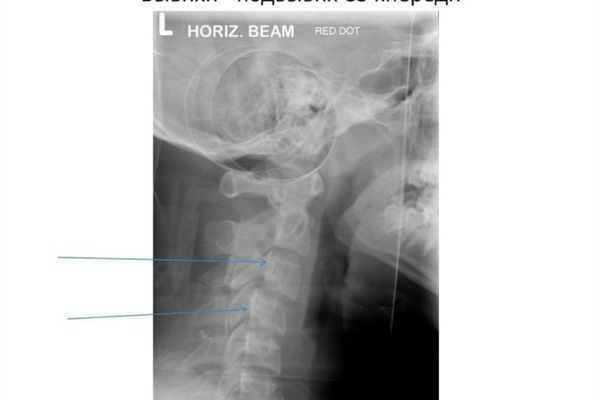

После визуального осмотра пациента и оценки симптомов ему назначают диагностические процедуры, которые включают:

Рентгенография. Выбор проекции подбирается индивидуально в каждом конкретном случае. Как правило, изображение делается как минимум в двух проекциях;